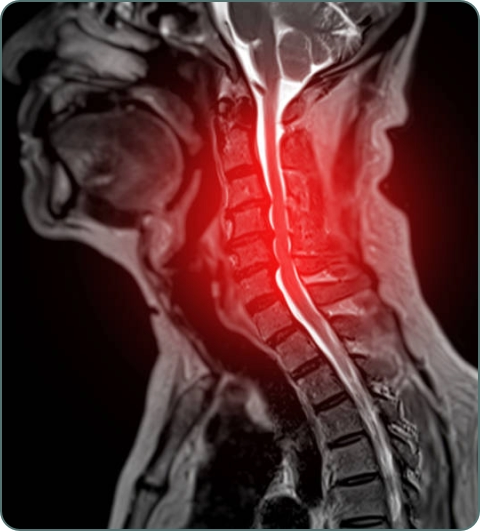

Back and Neck Pain

Chronic and acute pain in spine including herniated discs, sciatica, and cervical pain affecting daily activities and quality of life.